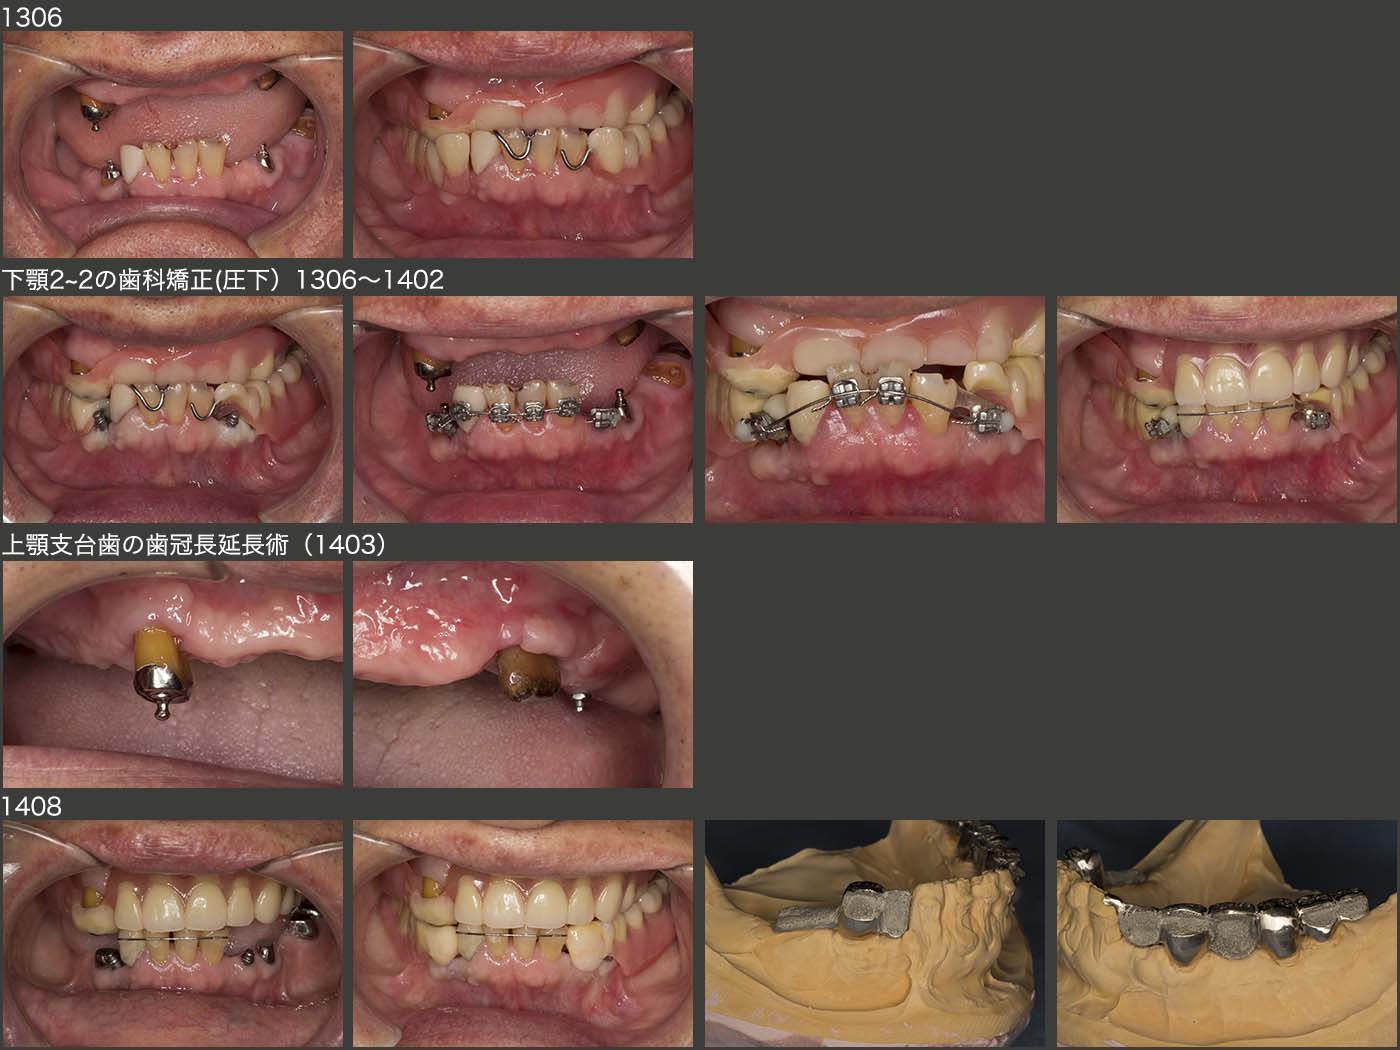

上段は2013年6月の状態.右上3,右下4(移植歯)および左下4に暫間のOPAアタッチメントを装着した.なお,左上のミニインプラントにもOリングゴムを装着してOPAアタッチメントの代役とした.

つぎに下顎の2〜2の挺出を元に戻すために,まず下顎左右2の遠心にミニインプラントを植立し,歯科矯正の際の固定源とした.約8ヵ月かけて2〜2を圧下させた.さらに,上顎義歯の咬合平面を整えるために,右上3および左上5(移植歯)の歯冠長延長術を施した.14年8月,基礎となる治療はすべて終了し,これより補綴処置に移行した.

2015年6月,初診終了時の状態.初診より3年2ヵ月が経過してしまった.患者さんには長い間通院してくださり,心より感謝する次第である.上下顎とも支台歯が左右側にあることから,義歯の安定はすこぶるよい.左上のミニインプラントは役目が終わったので本来なら除去すべきところであるが,特に問題もないことからこのまま置いておくことにした.